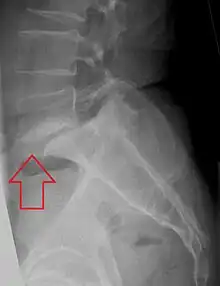

| X-ray of the lateral lumbar spine with a grade III anterolisthesis at the L5-S1 level | |

Classification by degree of the slippage, as measured as percentage of the width of the vertebral body:[14] Grade I spondylolisthesis accounts for approximately 75% of all cases.[6]

- Grade III: 50–75%